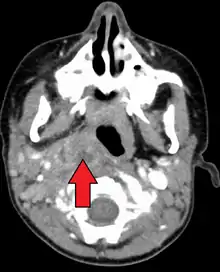

A computed tomography (CT) scan is the definitive diagnostic imaging test.[4]